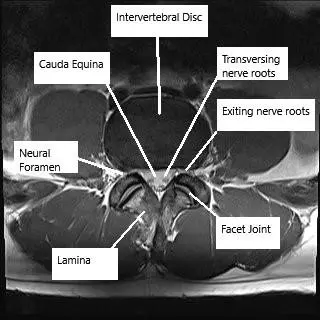

Resonancia magnética de la columna lumbar en corte axial y sagital

Resonancia magnética de la columna lumbar en corte axial y sagital.